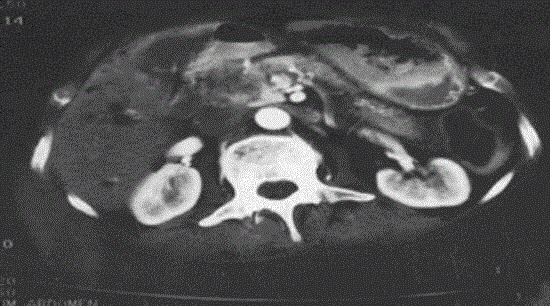

Figure 1. Pre radiofrequency ablation contrast enhanced computed tomography demonstrating large pancreatic head malignancy.